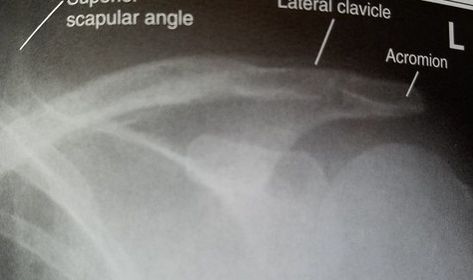

| AP Clavicle | ANATOMY: entire clavicle with both AC and SC joints included CRITERIA: entire clavicle and acromion are included lateral clavicle bows up, while the medial clavicle is superimposed by ribs 2-3 POSITIONING: CR perpendicular @ midclavicle |

| AP Axial Clavicle | ANATOMY: entire clavicle and both joints included CRITERIA: clavicle is more horizontal, and projected above the scapula and ribs medial end may be superimposed by ribs POSITIONING: CR angled 15-30 degrees cephalic @ midclavicle |

| AC Joints | ANATOMY: Bilateral AC joints included and open CRITERIA: non weight bearing and weight bearing projections marked correctly both joints included lateral clavicle almost horizontal POSITIONING: CR perpendicular @ jugular notch |